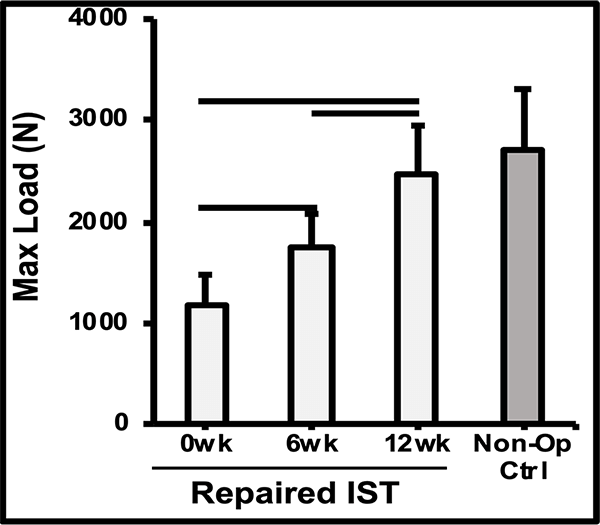

The mechanism of action was demonstrated in a preclinical sheep model, showing a thicker tendon at 6-12 weeks, and a repair that’s as strong as the native tendon by 12 weeks.1,2

MRI & Histology

Biomechanics